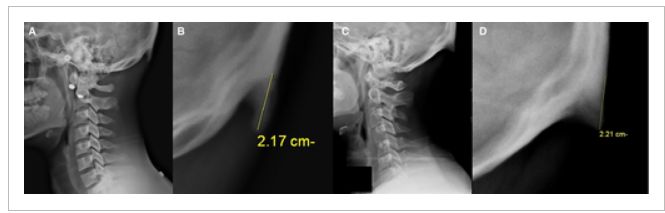

(A,B):A组参与者的X光片;(C,D)B组参与者的X光片;(B,D)分别在A,C中扩大了周围区域的图像,包括扩大的枕外隆突;(B,D)图像中的测量线,指示了扩大的枕外隆突的起点、尖端和长度

他们还发现男性枕外隆突的现象(67.4%)显著高于女性(20.3%),男性平均枕外隆突的大小(15±7 mm)也显著大于女性(10±4 mm)(P < 0.001)。男性参与者中最长的枕外隆突为35.7 mm,女性群体中最长的枕外隆突为25.5 mm。